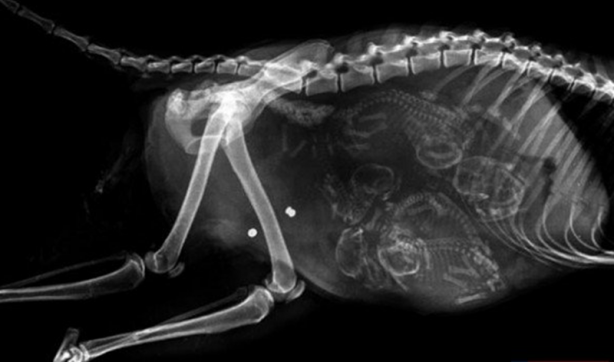

Hamile yarasa